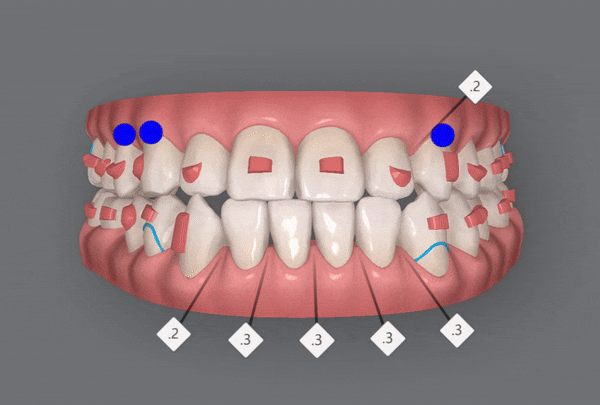

3rd(29개)

위 사진은 세번째 클린체크를 모두 마친후의 사진입니다

어금니들이 제 위치를 찾고 정중선이 맞춰졌습니다

환자분께서는

이상태로도 너무 만족해하셔서

여기서 교정 끝내도 될것 같다고 하셨어요 ㅎㅎ

HOWEVER,

완벽함을 추구하는 닥터킴은

마지막 클린체크를 이어가셨습니다!